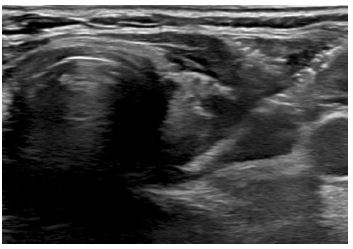

A 78-year-old female with a 10-year history of Hashimoto’s thyroiditis, biochemically on Levothyroxine 75 mcg daily presented to the endocrinology clinic with a 2-month symptom duration of unilateral left sided thyroid fullness and neck discomfort with asymmetric left thyroid enlargement confirmed on physical exam. An Ultrasound (US) of the thyroid and neck was significant for a unilateral increase in the size of the left thyroid lobe from 5.3×3.6×3.3 cm to 8.5×3.3×4.1 cm over 3 years and an enlarged left sided level 3 suspicious cervical lymph node measuring up to 1.4 cm in short axis, with loss of its fatty hilum (Figure 1).

Figure 1: Transverse view depicting newly enlarged left thyroid gland on ultrasound.